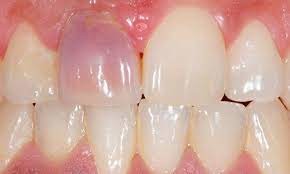

What causes a tooth to go black?

There are many reasons why a tooth can begin to go black, anything from simple staining to the death of the tooth can cause blackness and darkening.

The death of a tooth

When a tooth dies, the blood supply – which gives the tooth its natural, healthy color – will stop. Because the tooth is not receiving the nutrients it needs, it will begin to necrotise, darken, die and slowly go black.

Will my tooth go black after root canal?

A common misconception is that a tooth will go black after a root canal treatment. Teeth will often go black before root canal treatment as the tooth rots and decomposes on the inside. If root canal treatment is done well, all of the decomposing tissue will be removed and the blackness will not get worse. There may, however, be some mild darkening of the tooth after a root canal, depending on exactly how the root canal treatment is done and with which material.

How long does it take for a tooth to go black?

If the cause of the blackness is due to tooth decay, the blackness can happen over a period of years. If the cause of the blackness is due to trauma, as soon as the blood supply has been cut off from the tooth, the internal tooth tissue will begin to die and turn black.

Will a dead tooth go black?

If a dead tooth is left untreated, it will go black as the internal tooth tissue dies and decomposes. If the dead tooth has been root treated with a tooth-colored treatment, the tooth may not go completely black, although it may darken slightly.